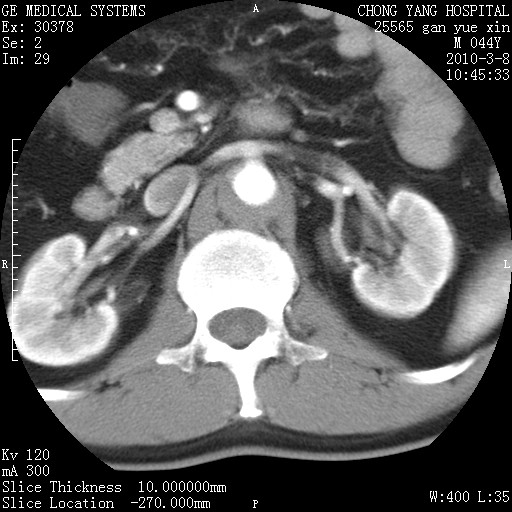

标题: CT24940:主动脉增强,典型病例。 [打印本页]

标题: CT24940:主动脉增强,典型病例。

夹层动脉瘤。

动脉夹层

夹层动脉瘤,典型

主动脉夹层。

动脉夹层的分型:

⒈debakey分型:根据主动脉夹层累及部位,分为三型:ⅰ型:原发破口位于升主动脉或主动脉弓部,夹层累及升主动脉、主动脉弓部、胸主动脉、腹主动脉大部或全部,少数可累及髂动脉。ⅱ型:原发破口位于升主动脉,夹层累及升主动脉,少数可累及部分主动脉弓。ⅲ型:原发破口位于左锁骨下动脉开口远端,根据夹层累及范围又分为ⅲa,ⅲb。ⅲa型:夹层累及胸主动脉。ⅲb型:夹层累及升主动脉、腹主动脉大部或全部。少数可累及髂动脉。

⒉stanford分型:a型:夹层累及升主动脉,无论远端范围如何。b型:夹层累及左锁骨下动脉开口以远的降主动脉。

夹层动脉瘤,少量胸水

夹层动脉瘤;左侧少量胸腔积液。

典型主动脉夹层。